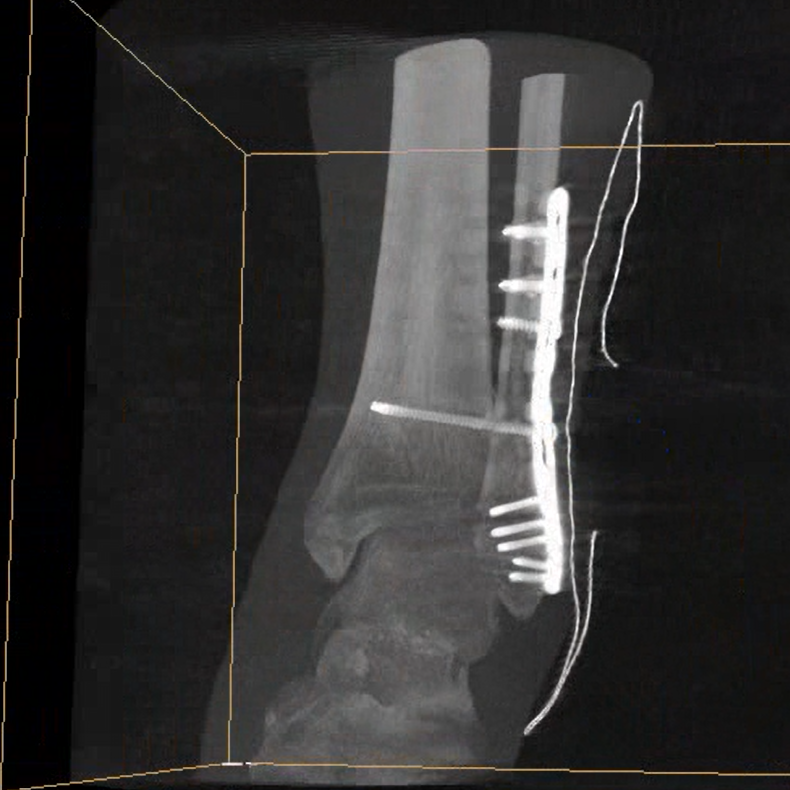

術(shù)中三維成像和橫斷面圖像提供多角度的手術(shù)診斷信息,輔助醫(yī)生進行術(shù)中評估判斷,諸如骨折復(fù)位情況和內(nèi)植入螺釘?shù)某叽绾臀恢?,輔助手術(shù)更好地完成。